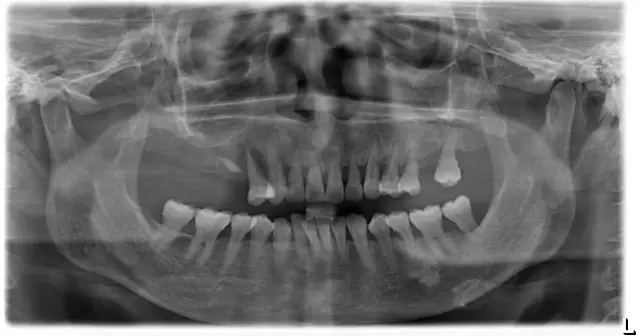

▲种植前

▲种植后